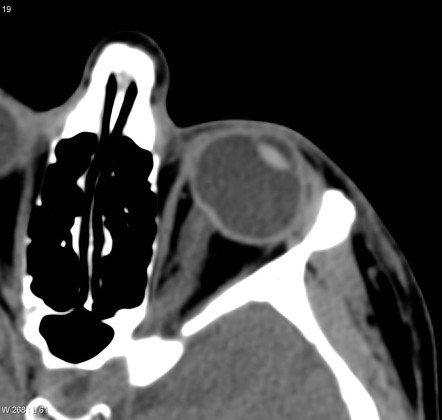

이부분을 사상판전층(Pre-laminar area)라고 합니다.

즉, 예상하다시피 바로 뒷부분에 사상판(lamina cribrosa) 라는 곳이 있습니다.

신경섬유들이 안구를 빠져나가는 곳에 있는 작은 세공(pore)가 수없이 많이 뚫려있는 판형태의 지역이 있는데,

이를 사상판(lamina cribrosa)라고 합니다.

즉, 실 사 (絲)를 써서 실과 같은 구멍 이 엄청나게 뚫려있는 판이라는 뜻으로

망막신경섬유층들의 가느다란 실들이 작은 구멍(cribriform)을 통해서 빠져나가는 판(lamina)입니다

이부분에는 직경 25~250um의 세공이 있고, 구멍주위에는 섬유성중격이 있고, 이를 도와주는 별아교세포(astrocyte)들이 존재합니다.

섬유성 중격과 별아교세포들은 세공을 지나가는 시신경섬유들을 기계적으로 보호하는 역할을 합니다.

위쪽과 아래쪽 사상판 부위의 세공이 귀쪽이나 코쪽보다 세공의 구멍이 크다고 알려져 있으며,

이부분은 주위에 아교질이 적습니다.

시신경을 보호하는 아교질이 적다보니, 녹내장에서 위쪽과 아래쪽의 사상판주위가 먼저 손상되는 것으로 생각되고 있습니다.